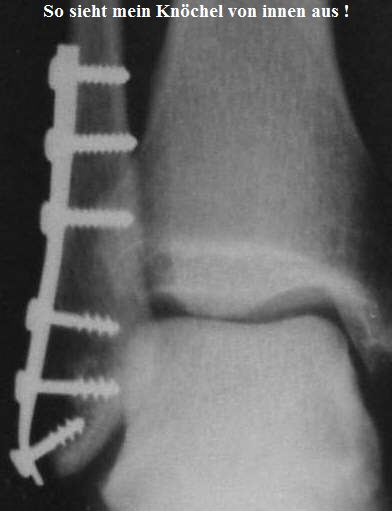

Hebbel's Fraktur

Am 12.08.2001 hab ich mir beim Fußballspiel den rechten Außenknöchel gebrochen !

Dieser Bruch nennt sich “Weber B Fraktur, rechts OSG”.

Am 15.08.2001 wurde ich in der Berufsgenossenschaftlichen Unfallklinik in Frankurt am Main operiert.

Hier ist ein schönes Röntgenbild von meinem Haxen !!

Zwischen der zweiten und dritten Schraube, von unten, war der Bruch.